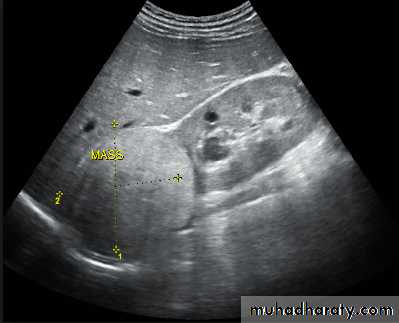

Ultrasound findings

1-Dilatation of the P.C.S. appears as multilocular fluid collection within central echo complex.-With more severe distention, dilated calyces appear as Multiple cysts but communicating with each other unlike true cysts.

2-Stones larger than 5 mm are easily seen on US but smaller ones may be missed.

-They produce intense echoes (hyperechoic) and cast acoustic shadows.

-Proximal and distal ureteric dilatation can be easily identified unlike mid-ureteric dilatation, and stones located in the middle third of the ureter are hard to be demonstrated unlike upper and lower ureteric stones (especially those lodged in the vesico-ureteric junction or pelvi -ureteric junction) which are easily identified by ultrasound.